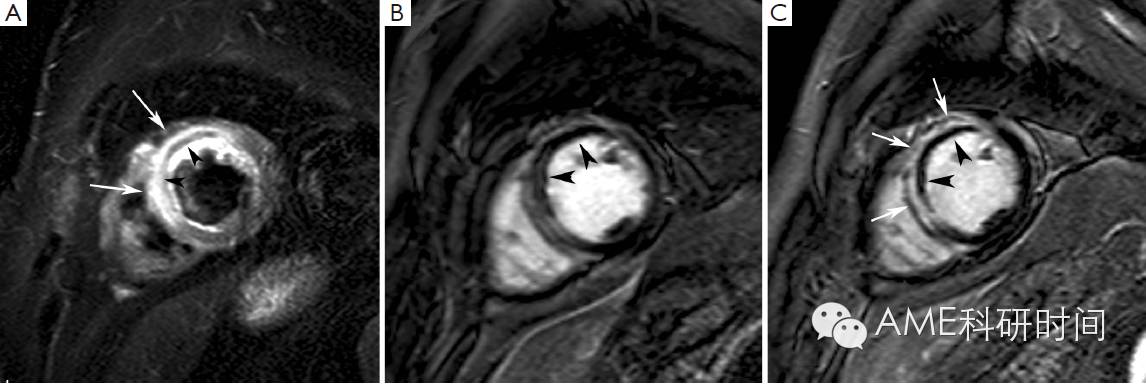

在过去的几年里,越来越多的证据表明,通过短时间反转回复序列(STIR) T2加权像的影像数值,可以判断危险心肌,即在冠状动脉阻塞时可通过再灌注得到挽救的心肌(2)。事实上,T2加权像STIR对组织游离水(水肿)的增加特别敏感,而游离水的增加通常伴随缺血性心肌损伤,无论组织是否坏死(3,4)。心肌水肿(缺血引起ATP依赖的钠钾离子通道的功能紊乱,导致膜两侧钠离子梯度的改变,从而引发细胞内水肿)是缺血性损伤的早期症状,T2加权像STIR成像对于在急诊中患有不稳定型心绞痛和不断发展的心肌梗死患者是一种非常有用的诊断手段(5,6)。尤其是在T2加权像STIR影像中,心肌水肿会呈现出强烈信号(亮)(见图1)。Abdel-Aty等人(7)的最近研究显示,通过水肿造影描绘了在缺血发生后30分钟内及不可逆性心肌损伤[表现为肌钙蛋白水平增高和迟发钆增强(LGE)]前急性心肌损伤的情况。Aletras等人(2)用实验证明了在发生再灌注心肌梗死两天后的T2加权像STIR影像中,水肿的面积对应于在发生冠状动脉阻塞时微球注射所呈现的危险心肌的面积(即参考标准)。此外,危险心肌面积明显大于最终发生梗死的心肌面积,说明在T2加权像STIR影像中呈现的水肿区域同时包括了可逆和不可逆损伤的心肌(即永久性心肌损伤)。最近在再灌注后ST-段抬高的心肌损伤患者中,使用单光子发射计算机断层成像术(SPECT)对这项技术进行检验。在急性心肌梗死7天后,使用经皮冠状动脉介入治疗前,通过99mTc-替曲膦SPECT看到的灌注不足区域与通过T2加权像STIR影像检测到的心肌水肿区域相似(8)。因此,T2加权像STIR成像术能够在不干扰急性期患者诊治的情况下,对危险心肌组织进行准确的、可回顾的和非电离的检测。此外,在急性再灌注心肌梗死的病人中,我们和其他一些研究组证明此技术得到的结果和血管造影术对危险心肌评分结果的一致性(9,10)。然而,最近有人对T2加权像STIR成像描绘危险心肌组织的准确性产生怀疑,因为它具有对人造品固有的高灵敏度和可重复性差(11)。此外,此技术的操作序列导致信噪比低及易于在心内膜和心室腔的边界检测到“血流慢”的假象。重要的是,我们对T2加权像STIR成像所确定的危险心肌组织的认识来源于数量相对较少的试验研究,需要进一步的研究。在这种情况下,产生了更好的序列产生了,例如T2加权稳定态自由旋进造影或T2弛豫时间图(12,13)。众所周知,T2加权异常在急性和亚急性预后阶段表现最明显,但是随梗死诱发的心肌水肿和炎症的再吸收而慢慢退去(8)。因此,T2加权STIR的序列能够将急性和慢性心肌梗死区分开来(14),因为在T2加权STIR成像中前者伴随着心肌水肿,而后者没有显现水肿。最后一点,T2加权STIR成像能够显现再灌注后心肌出血情况。事实确实如此,无再灌注的心肌梗死,一般不会导致出血,而再灌注的梗死不同与此,经常出现由缺血性再灌注引起的严重微血管损伤,从而导致明显的红细胞渗出(15)。活体和尸检研究显示通过检测血红蛋白降解物的顺磁性,T2加权具有辨别心肌内出血的能力,这将缩短T2弛豫的时间(16,17)。因此,水肿的图像显示出血性梗死区域的不均一性,通常呈现低亮度的核心和高亮度的边缘,因此可与非出血性梗死区别开来,因为非出血性梗死呈现亮度均匀的心肌(图2)。对98位患有再灌注ST段抬高的心肌梗死患者研究,发现25%的患者心肌内出血(18)。这些出血性梗死的患者出现更大的梗死面积和透壁性心梗,更大的无复流区和更少的心肌复活。心肌内出血,是独立于初始梗死面积,不利于左心室重塑的因素。之后,Eitel等人(19)研究发现T2加权检测出心肌出血,预测心肌梗死后6个月发生重大心血管疾病。

图2 Hemorrhagic myocardial infarction. Short-axis T2-weighted STIR imaging (A), early gadolinium imaging (B) and late gadolinium imaging (C) in a patient with an extensive reperfused acute anteroseptal myocardial infarction. Presence of an extensive zone of myocardial edema in the LV anteroseptal wall (arrows, A) with evidence of concomitant myocardial hemorrhage (arrowheads, A). On early gadolinium imaging, a large zone of microvascular obstruction is present (arrowheads, B). At late imaging, a significant shrinkage of the microvascular obstruction has occurred (arrowheads, C) while the infarct has substantially become enhanced (arrows, C). Adapted from Ischemic Heart Disease by Bogaert J and Dymarkowski S, in Clinical Cardiac MRI Second Edition, Bogaert J, Dymarkowski S, Taylor AM, Muthurangu V (eds). Springer Heidelberg, Germany (ISBN 978-3-642-23034-9).